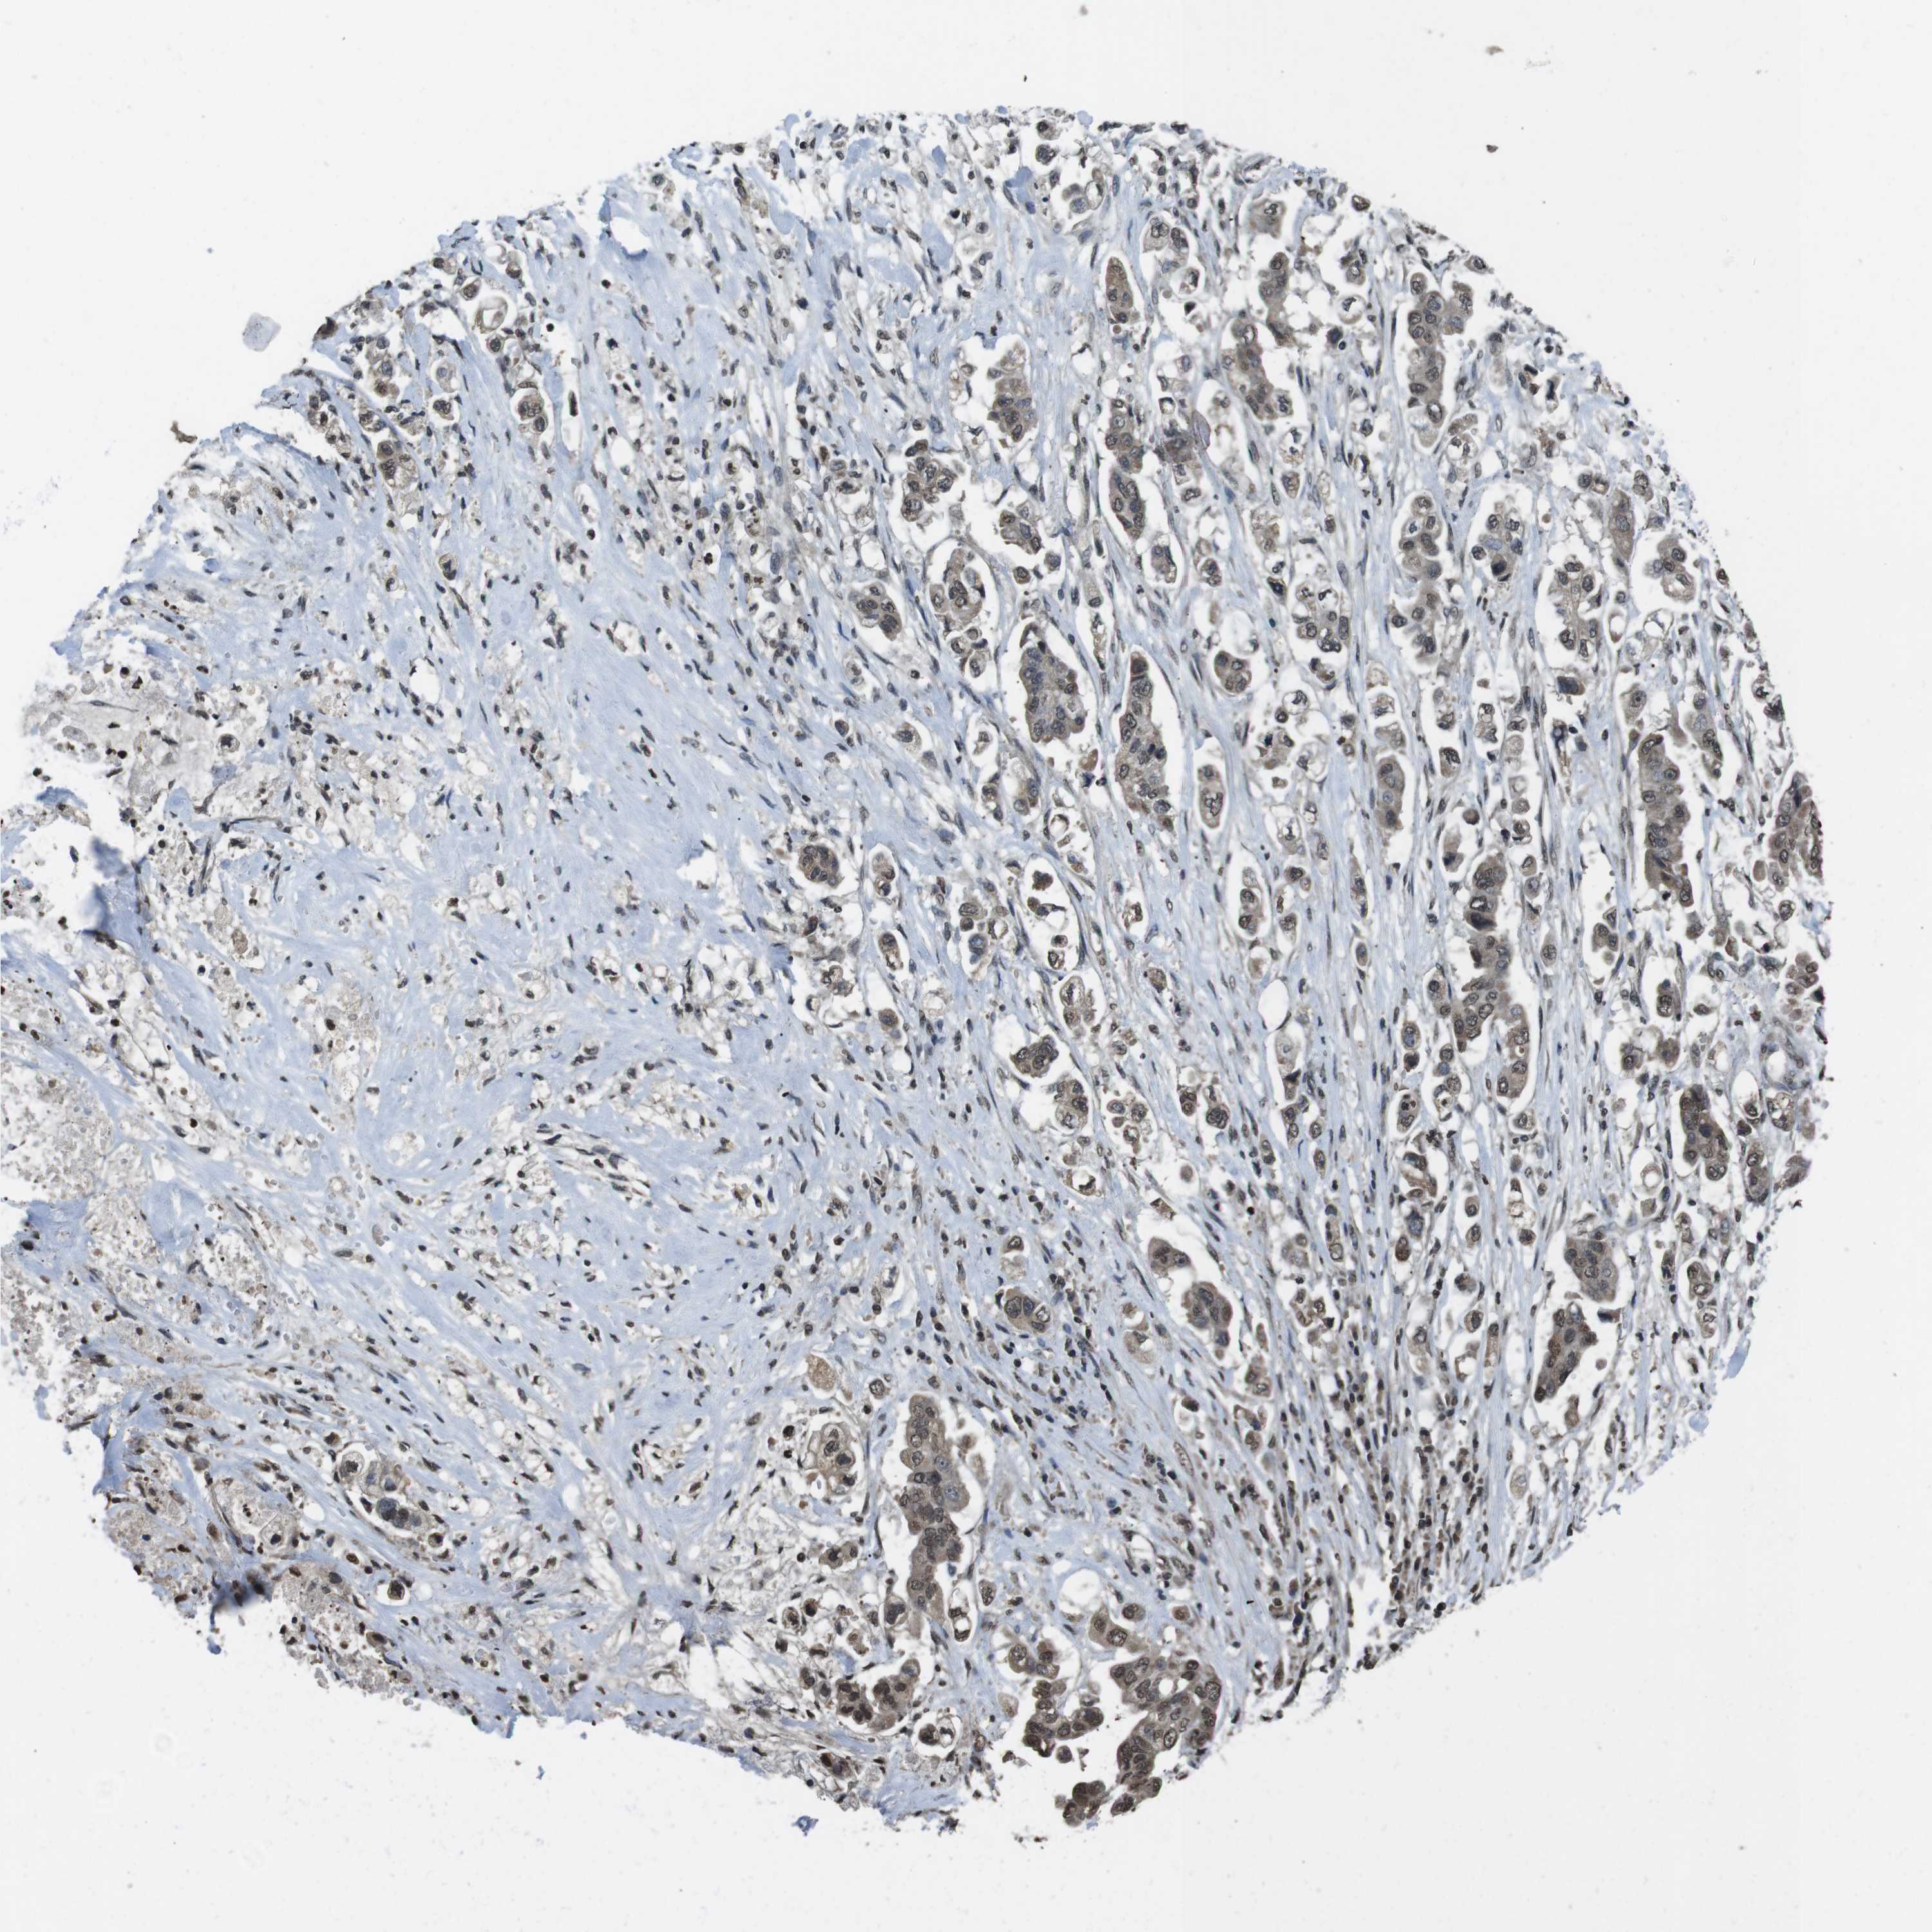

STOMACH CANCER - Protein expressioni

A mouse-over function shows sample information and annotation data. Click on an image to view it in a full screen mode. Samples can be filtered based on level of antibody staining by selecting one or several of the following categories: high, medium, low and not detected. The assay and annotation is described here.

Note that samples used for immunohistochemistry by the Human Protein Atlas do not correspond to samples in the TCGA dataset.

Antibody stainingi

Antibody staining in the annotated cell types in the current human tissue is reported as not detected, low, medium, or high, based on conventional immunohistochemistry profiling in selected tissues. This score is based on the combination of the staining intensity and fraction of stained cells.

Each image is clickable and will lead to virtual microscopy that enables deeper exploration of all samples and also displays staining intensity scores, fraction scores and subcellular localization as well as patient and tissue information for each sample.

Antibody HPA028289

Antibody CAB010296

Staining

High

Medium

Low

Not detected

Intensity

Strong

Moderate

Weak

Negative

Quantity

>75%

75%-25%

<25%

None

Location

Nuclear

Cytoplasmic/membranous

Cytoplasmic/membranous,nuclear

Adenocarcinoma, NOS

Adenocarcinoma, High grade